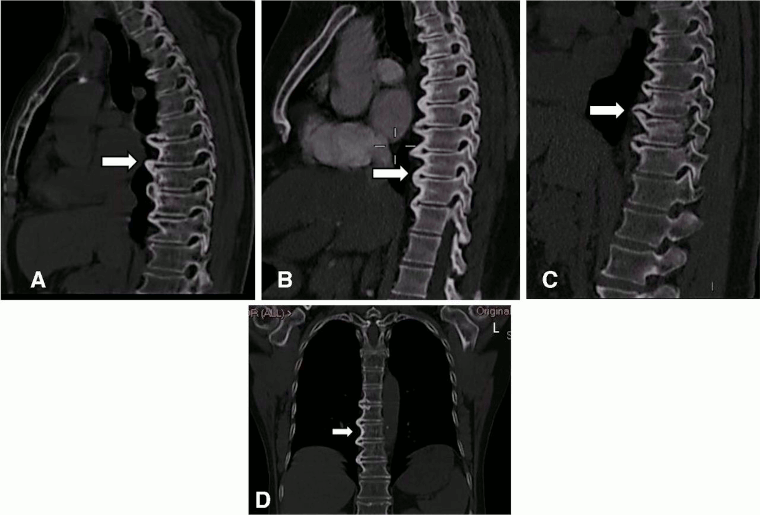

Although spine radiography is the investigation of choice for identifying characteristic bone formation, CT may also be considered.[4]

CT may be useful for detection of early changes secondary to DISH, and is a more sensitive imaging modality than x-ray in showing structural changes; however, this must be weighed against the harm of additional radiation exposure.

Criteria have been proposed to identify patients with early DISH on CT.[38] A score from 0 to 3 is assigned for each vertebral segment adjacent to a complete bone bridge, depending on presence of osteophytes, near complete bridging (<2 mm distance between bony structures), and complete bridging (full connection between two adjacent bones with abundant new bone formation).[38] The presence of <3 adjacent segments with a complete bone bridge is identified as early DISH, while the presence of ≥3 is labelled as definite DISH.[38]

[Figure caption and citation for the preceding image starts]: CT images of the thoracic spine in DISH. (A–C) Sagittal: CT scan images of anterior flowing osteophytes (arrows). (D) Coronal: dish of the thoracic spine (arrow) reconstructed from the chest CT scan. L = leftMader R, et al. RMD Open 2020; 6: e001151. doi: 10.1136; used with permission [Citation ends].

Other indications for CT include fracture detection and assessment of dysphagia.[1][3]

Request a whole-spine CT scan for patients with suspected spinal fractures. It can be challenging to identify spinal fractures in DISH on plain radiographs, due to the presence of degenerative changes and occult fracture lines, and whole-spine CT can provide a clearer view in patients with suspected spinal fractures.

may reveal presence of large bridging osteophytes and ossification of the anterior lateral ligament; may reveal spinal fracture